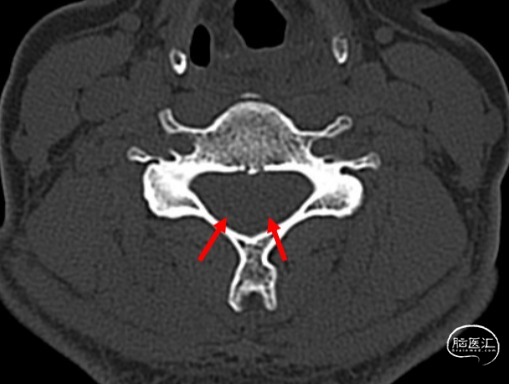

患者,女,36岁,因“头痛6天”入院于2002.5.19,入院后考虑“自发性低颅压头痛”,腰穿测压25mmH2O。行全脊髓MRI水成像未见异常,遂行全脊髓MRI造影术提示:颈1.2间左右两处瘘口分别位于颈1椎板上下缘。行DSA下精准靶向硬膜外血贴治疗后,患者第二天症状明显改善,第三天即痊愈出院。嘱患者两周后复查,因患者恢复满意,2周后患者不愿再做复查。